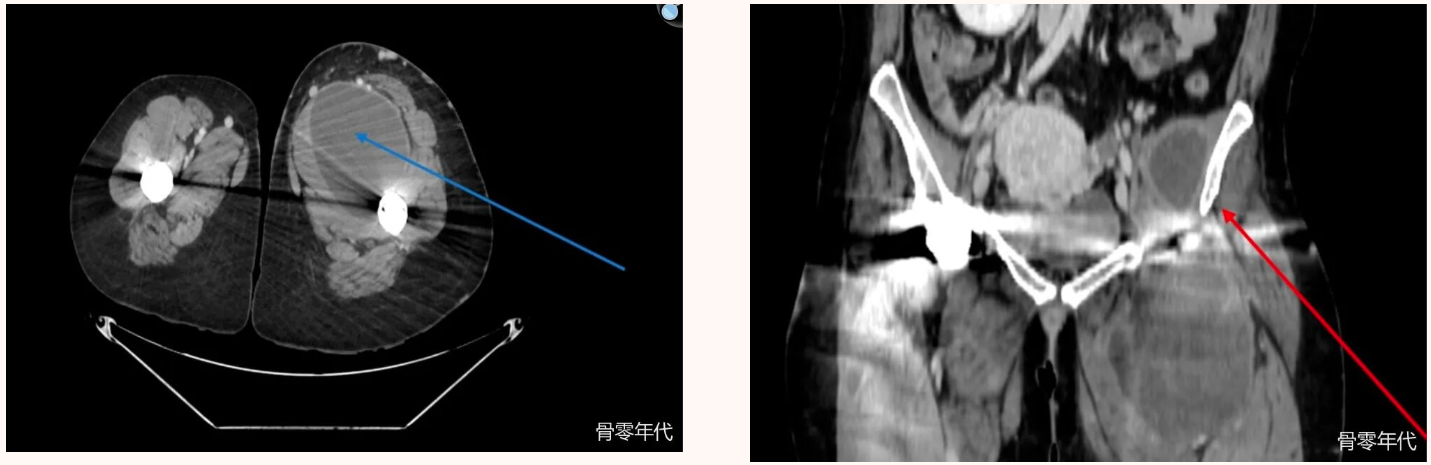

血管造影CT,轴面,髋部区域。以蓝色箭头标记的大型囊性病变与髋关节囊相连,并附有液体。血管造影CT,冠状平面,髋部区域。左侧半骨盆靠近髂骨内侧,标有红色箭头标记的积液。